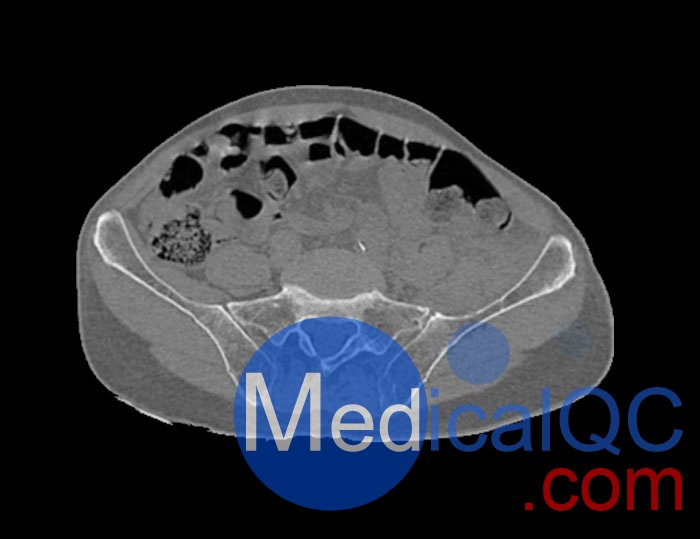

左側(cè)股骨頸移位骨折。

骨骼和軟組織的逼真模擬。